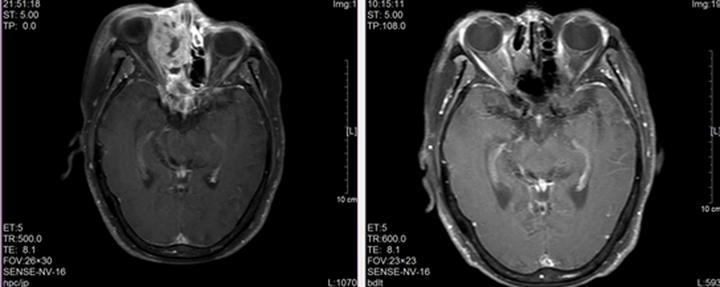

▲田阿姨接受治疗前、后的医学影像

治疗期间,田阿姨的症状逐渐缓解,3个月后复查,肿瘤已完全消退。如今五年过去,田阿姨不仅达到了临床治愈,还完好保住了双眼,日常生活和普通人一样,安享晚年。